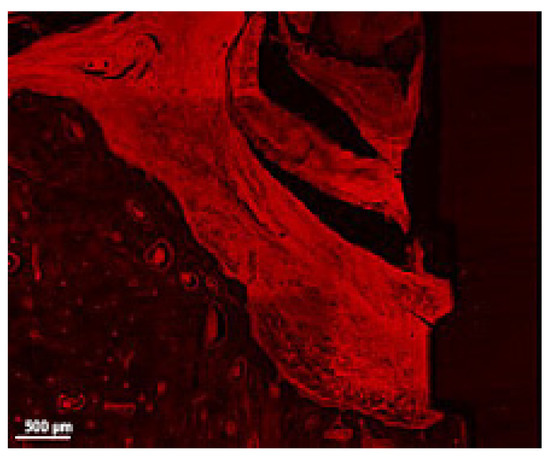

Figure 7.

Detail of the soft tissue and bone in a thick section of a ligated implant. Note the presence of ligatures in the upper central region of the image, the highly inflamed soft tissue in contact with bone and implant surface, the minimal presence of Howship lacunae and the congested venules (implant #5, buccal aspect, bar, 500 µm).

There are several advantages of CLSM over LM, as a good method to identify both soft and hard tissue modifications, especially when analyzing thicker sections, that tend to appear opaque in LM: there are no laborious staining protocols because CLSM uses intrinsic fluorescence; the “thick” sections can be easily manipulated by hand; it can provide 3D reconstructions. Particular disadvantages of CLSM when compared to LM resulted from the observation of this study: the ICT, a relatively important area when describing the inflammation in peri-implantitis, cannot be identified neither characterized properly without supplementary fluorescent labelling (Figure 7), same for the limit of the squamous epithelium (aJE) that did not appear clearly visible on many sections (Figure 6).